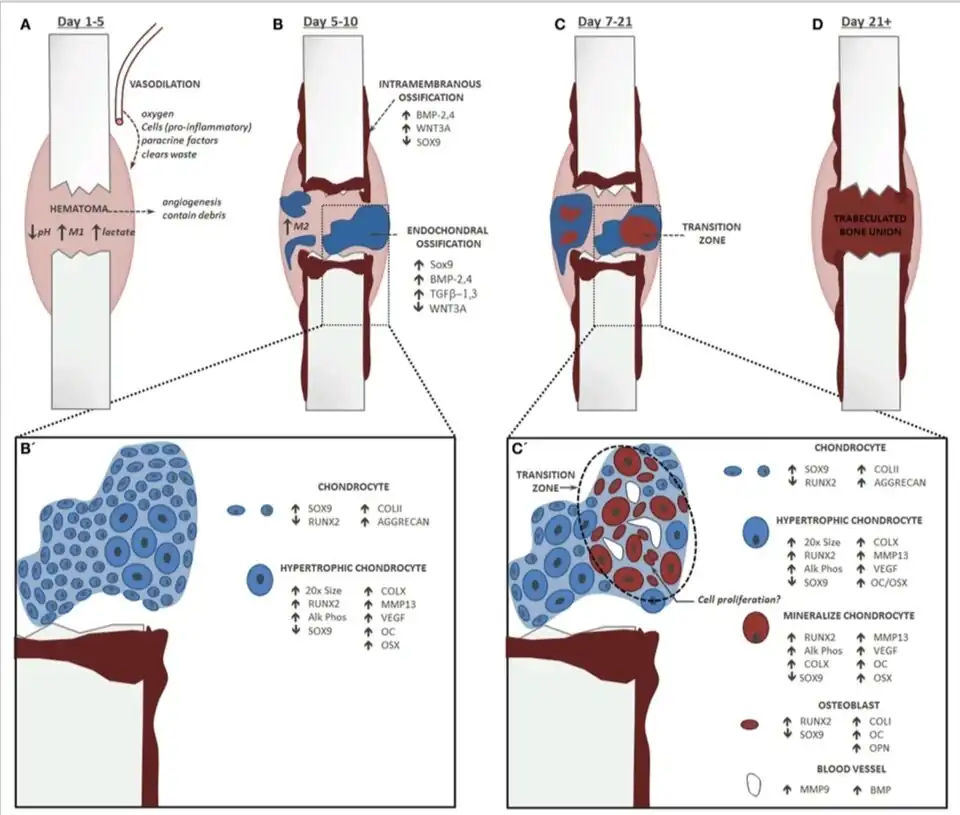

Dit heeft tot gevolg dat een open breuk rechtstreeks in contact kan komen met kiemen die een infectie kunnen veroorzaken. Bijkomend probleem is dat het botweefsel maar weinig bevloeid wordt en dus slecht bestand is tegen besmetting. Het kan niet rekenen op de goede humorale verdediging vanuit het bloed. Een open breuk loopt dus een groot risico op infectie en dient dus steeds preventief behandeld te worden met antibiotica. Nog een laatste bijkomend probleem bij open botbreuken is de tragere botheling omdat er zich geen hematoom kan vormen. Dit belemmert de natuurlijke genezing, de genezing door callusvorming. Callusvorming is de natuurlijke manier, waarop een breuk in een bot weer dichtgroeit.

Genezen

De actieve genezing kan op twee manieren geschieden:

- Genezing per primam, met een orthopedische of chirurgische ingreep, waarbij de botstukken aan elkaar worden gezet (absoluut stabiele fixatie) met behulp van platen en schroeven.

- Genezing per secundam, het bot natuurlijk laten genezen, maar het geblesseerde lichaamsdeel extra verzorgen. Hierbij vindt callusvorming plaats.

Vaak wordt een gipsverband aangebracht om de posities van de botstukken ten opzichte van elkaar te fixeren. Vaak is het nodig, om zelfs nadat het bot goed is genezen, te revalideren. Het kan dat de plaats om het bot, waar het gebroken is geweest, gevoelig blijft.